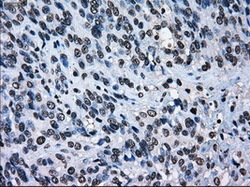

- Immunohistochemical staining of paraffin-embedded Adenocarcinoma of endometrium tissue using anti-ERCC1 mouse monoclonal antibody. (Dilution 1:50).